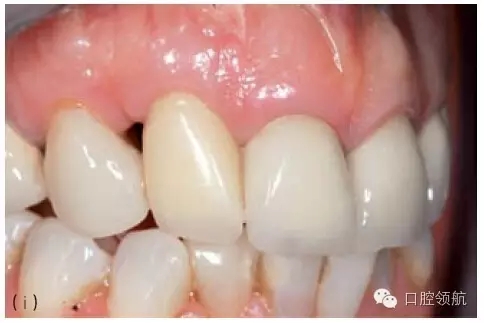

當(dāng)植入位置不佳不能以軟組織移植來(lái)挽救,而患者又要求達(dá)到良好的美學(xué)效果,除了取出種植體重新開(kāi)始之外,別無(wú)選擇。取出種植體后通常需要進(jìn)行骨增量,之后在正確位置上植入新種植體。對(duì)于局部骨增量,推薦引導(dǎo)骨再生(GBR)技術(shù),可同期或分階段進(jìn)行。外科方法的選擇主要取決于取出種植體時(shí)造成骨缺損的范圍和形態(tài)。任何時(shí)候,盡量在種植體植入同期行GBR,這時(shí)候一般是二壁骨缺損,如此可以避免患者接受額外的手術(shù)程序。然而,取出種植體導(dǎo)致的一壁骨缺損需要分階段的方式,首次骨增量采用自體骨塊移植加膠原膜覆蓋,5~6月后再植入種植體。這些治療需要患者和醫(yī)生的合作,通常可以獲得不錯(cuò)的美學(xué)效果(圖8.26a~g)。

圖8.26 (a)一個(gè)非常嚴(yán)重的病例:上頜前牙區(qū)植入3顆種植體。首先,考慮到美學(xué)效果,應(yīng)該只在8號(hào)和11號(hào)位點(diǎn)植入2顆種植體;其次,8號(hào)種植體冠向植入位置不佳伴肩臺(tái)外露。3顆種植體都需要取出。(b)種植體取出術(shù)中應(yīng)做避開(kāi)齦乳頭的小切口,盡量減少創(chuàng)傷。(c)翻開(kāi)黏骨膜瓣后清楚可見(jiàn)唇側(cè)骨缺損。在種植體鄰面小心去骨,盡量減少唇側(cè)去骨。(d)取出3顆種植體后的臨床情況。骨缺損處清創(chuàng),膠原塞填充。(e)手術(shù)完成,初期傷口關(guān)閉需達(dá)到軟組織完整覆蓋缺牙區(qū)。6~8周后種植體植入并同期行GBR。(f)植入2顆種植體和局部GBR骨增量治療3年后的效果。用低替代物含量的骨充填物(去蛋白小牛骨礦化基質(zhì))行橋體區(qū)域垂直骨增量。(g)3年隨訪檢查的X線片。新植入的2顆種植體顯示出穩(wěn)定的種植體周骨水平,尤其在橋體區(qū)域。